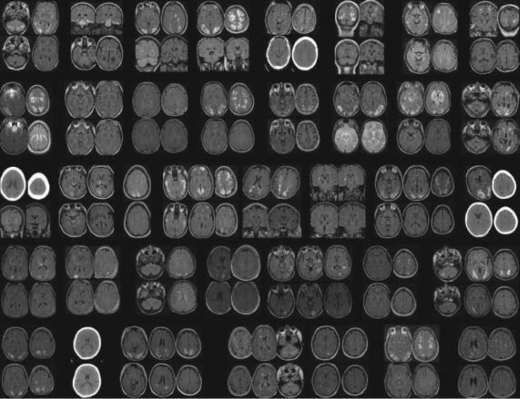

התמונה ההדמייתית האופיינית ב- CT או Magnetic Resoance Imaging) MRI) היא של בצקת מוקדית סימטרית. האונות האוקסיפיטליות (Occipital) והפריטאליות (Parietal) הן המעורבות בשכיחות הגבוהה ביותר ואחריהן האונה הפרונטאלית (Frontal), החלק התחתון של החיבור בין האונה הטמפוראלית (Temporal) והאוקסיפיטאלית ולבסוף הצרבלום (Cerebellum).

הממצא האופייני ב-MRI הוא היפראינטנסיות (Hyperintensity) ברצף T2 הנגרמת כנראה בשל בצקת ואזוגנית תת-קליפתית של החומר הלבן. ממצאים פתולוגיים בולטים אף יותר ברצף FLAIR (Fluid Attenuated Inversion Recovery) אשר מאפשר להבחין בשינויים עדינים.

בנוסף, שימוש ברצפי Diffusion-Weighted Imaging) DWI) ו-Apparent Diffusion Coefficient) ADC), עוזר להבדיל בין בצקת ואזוגנית, שהיא המרכיב המשמעותי ב-PRES, לבין בצקת ציטוטוקסית (Cytotoxic) שמאפיינת נזק מוקדי איסכמי (תמונה 1).

בבצקת ואזוגנית שהיא המרכיב העיקרי ב-PRES, האזורים ההיפראינטנסיים ב-T2 מתאימים ב-DWI לאזורים היפראינטנסיים או איזואינטנסיים (Isointense). ב-ADC אזורים אלה יראו גם הם בהירים יותר, בניגוד לנזק איסכמי (המבטא בצקת ציטוטוקסית) בה יראו אזורים אלה ב-ADC כהים.

רוב הנגעים ב-PRES לא עוברים האדרה עם גדוליניום (Gadolinium). האדרה באזורים ההיפראינטנסיים ב-T2 תתכן בחולים בודדים ויכולה להעיד על דינמיות של הנגעים וחומרתם וקשורה גם לפרק הזמן שחלף מאז תחילת התסמינים.

רזולוציה (Resolution) מלאה של ממצאי ההדמיה נחשבת כמעט כהגדרה של התסמונת על אף שלא ברור התזמון המיטבי לביצוע הדמיית ביקורת (תמונה 2), אך היא מתרחשת כנראה בין פרק זמן של ימים בודדים עד שבועות [11], [2]. על אף התמונה המתוארת כאופיינית, קיימים מקרים רבים בהם ההדמיה אינה תואמת את תיאור זה. תוארו מקרים עם מעורבות קדמית משמעותית. יש גם מקרים מתועדים של מעורבות קורטיקאלית (Cortical), נזקים בלתי הפיכים נקודתיים, דימומים לתוך נגעים ומעורבות חד צדדית (תמונה 3).